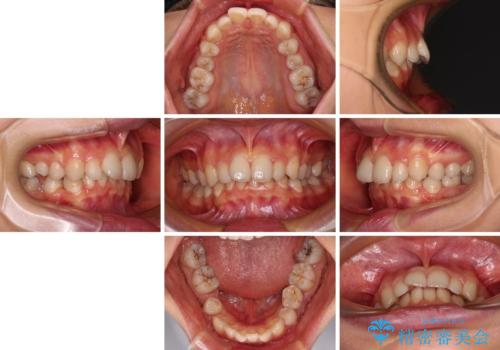

欠損や残存乳歯、深い咬み合わせ ワイヤー矯正で咬合改善

- 後続永久歯の欠損によるスペースと残存乳歯、深い咬み合わせを気にして来院された患者様です。

乳歯を残し、欠損部位のスペースを適正な幅に拡大し、インプラント補綴治療により歯列を整える治療も考えられましたが、ご本人から飛び出している前歯をどうしても引っ込めたいとの要望があったため、残存乳歯ならびに上顎左右第二小臼歯を抜歯して、歯列を整えることとしました。